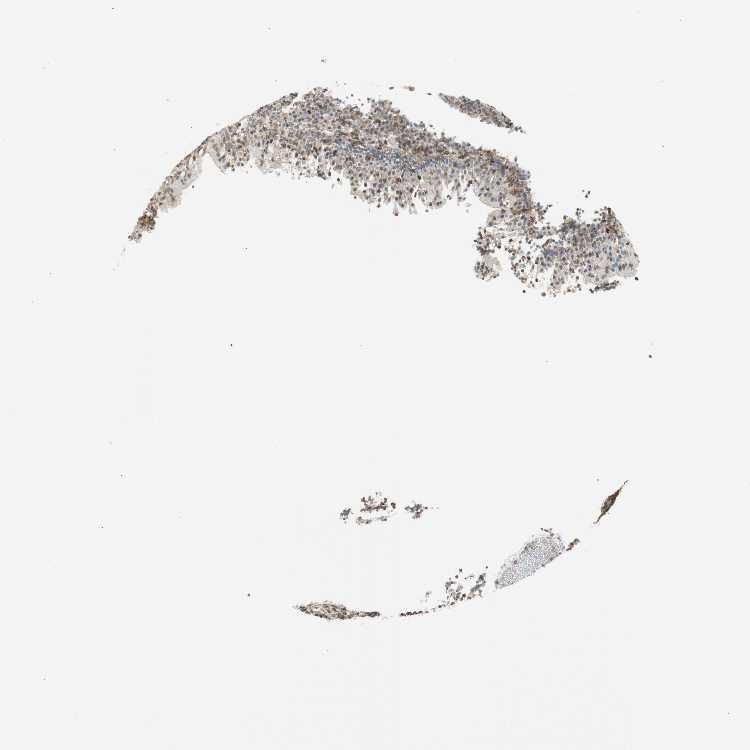

TONSIL - Antibody stainingi

Antibody staining in the annotated cell types in the current human tissue is reported as not detected, low, medium, or high, based on conventional immunohistochemistry profiling in selected tissues. This score is based on the combination of the staining intensity and fraction of stained cells.

Each image is clickable and will lead to virtual microscopy that enables deeper exploration of all samples and also displays staining intensity scores, fraction scores and subcellular localization as well as patient and tissue information for each sample.

Antibody HPA046833Antibody CAB004545

Germinal center cells MediumMedium

Non-germinal center cells MediumLow

Squamous epithelial cells LowMedium